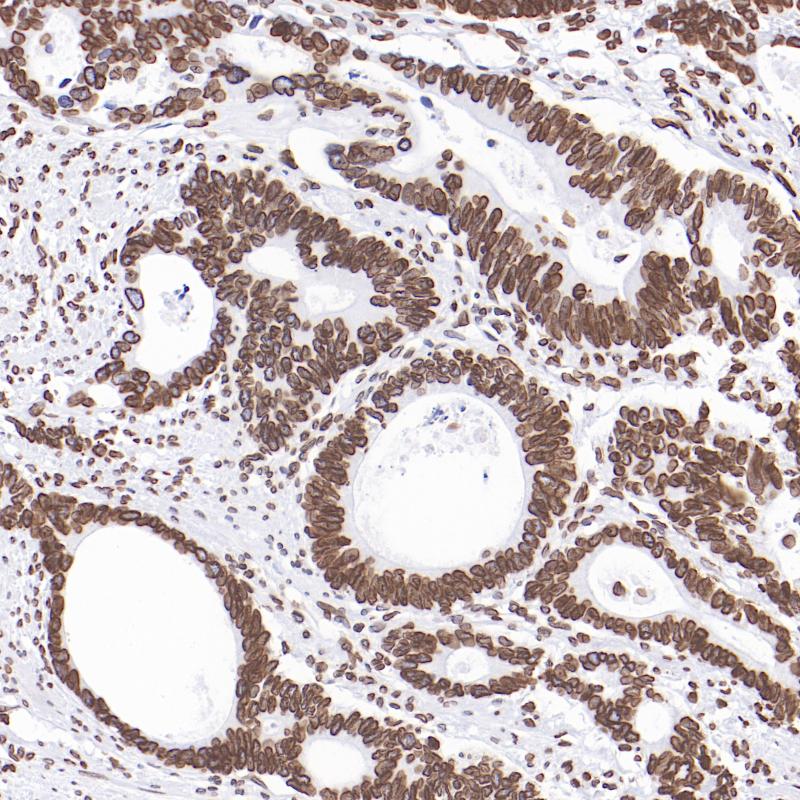

Lamin B1 重组兔单克隆抗体

阳性对照

结肠癌

亚细胞定位

Nucleus inner membrane